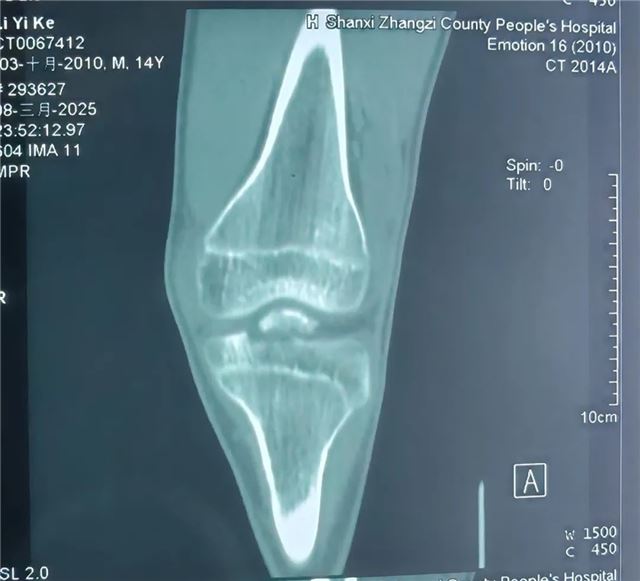

近日 长治二院小儿骨科团队 成功完成首例 关节镜下胫骨髁间棘骨折复位固定手术 标志着 长治二院小儿骨科 在青少年运动损伤及关节 微创治疗领域又上新台阶! 术前 术中 该手术通过仅0.5cm的微小切口,结合高清关节镜技术,实现骨折精准复位与牢固固定,术后患者无疼痛、恢复快,早期可下地活动,为青少年患者提供了更优治疗方案。 技术亮点 创伤极小:避免传统开放手术的大切口,减少软组织损伤。 精准高效:关节镜高清视野助力精准复位,固定牢靠。 康复迅速:术后早期功能锻炼,缩短住院时间,降低并发症风险。 美观无忧:微创切口隐蔽,术后疤痕几乎不可见。 适应人群 运动损伤致胫骨髁间棘骨折患者。 膝关节外伤后疼痛、活动受限者。 追求微创、快速康复的青少年患者。 咨询电话: 主任医师任泽恩:13008078999 周一、周五、周六上午专家门诊 主治医师牛佳伟 18834181790 周日上午节假日门诊 科普园地 01 胫骨髁间棘骨折是什么? 胫骨髁间棘是膝关节内交叉韧带附着的重要结构,骨折多由运动损伤(如急停、扭转)或高能量外伤(如车祸)导致,表现为膝关节剧痛、肿胀、无法伸直,易误诊为韧带损伤。 02 传统手术 vs 关节镜微创手术 传统开放手术:需切开关节囊,创伤大、恢复慢,可能遗留关节僵硬。 关节镜手术:通过2-3个5mm小孔完成,镜下精准复位骨折块,配合可吸收螺钉或缝线固定,最大程度保护关节功能,术后可早期开始康复锻炼。 03 术后康复小贴士 早期冰敷+踝泵训练,减轻肿胀 术后2周内拄拐部分负重,逐步过渡到全负重 4-6周后结合理疗加强膝关节活动度与肌力 微创技术,让运动之痛不再成为人生绊脚石!长治二院小儿骨科将持续深耕关节微创领域,以尖端技术守护儿童“膝”望! 名医推荐 任泽恩 主任医师、教授 骨科党支部书记 小儿骨科病区主任 硕士研究生导师 牛佳伟 主治医师 骨科学硕士 【专业特长】 儿童创伤保守和手术的微创治疗。四肢畸形矫正(先天性或创造成的肢体内外翻、肢体不等长等)。手足部多指/趾畸形、并指/趾畸形等。曾于北京参加“骨外固定与肢体重建基础实战技术培训班”。 科室简介 小儿骨科于2019年创立,现病床配置18张,科室现有主任医师1名,副主任医师1名,主治医师1名,住院医师1名,其中硕士研究生2名,硕士研究生导师1名,目前是长治地区唯一专业诊治儿童骨骼疾病的专业科室,年门诊量5000余人次,年手术近500例。 科室成立5年来,我们小儿骨科团队同心协力,追求卓越,推动学科快速发展。我们小儿骨科开展的多项手术技术处于省内领先地位,辐射影响达周边地市,在上党地区享有盛誉,得到了国内、省内业内同行及患者家属的高度认可。目前以京长合作为契机积极与北京积水潭医院小儿骨科紧密合作,成立了“吕学敏教授团队名医工作室”,定期派专家来我院坐诊、讲学、查房,开展新技术新项目、疑难病例会诊及手术指导。大大提高了诊疗疑难疾病的能力。 诊疗范围:14周岁以下的儿童骨病患者(含14周岁)。目前已经开展的技术项目:小儿四肢关节创伤微创手术治疗、部分小儿先天性及发育性畸形矫正、四肢与关节特异性及非特异性炎症、儿童各类软组织疾患及骨肿瘤。(肱骨髁上骨折闭合复位经皮克氏针内固定、儿童四肢骨干骨折弹性髓内针内固定、青少年股骨干骨折交锁髓内钉内固定、肘关节关节内骨折手术治疗、手足多指(趾)畸形切除及矫形术)。 编 辑丨翟艳鹏 初审初校丨牛佳伟 复审复校丨任泽恩 终审终校丨雷 赫